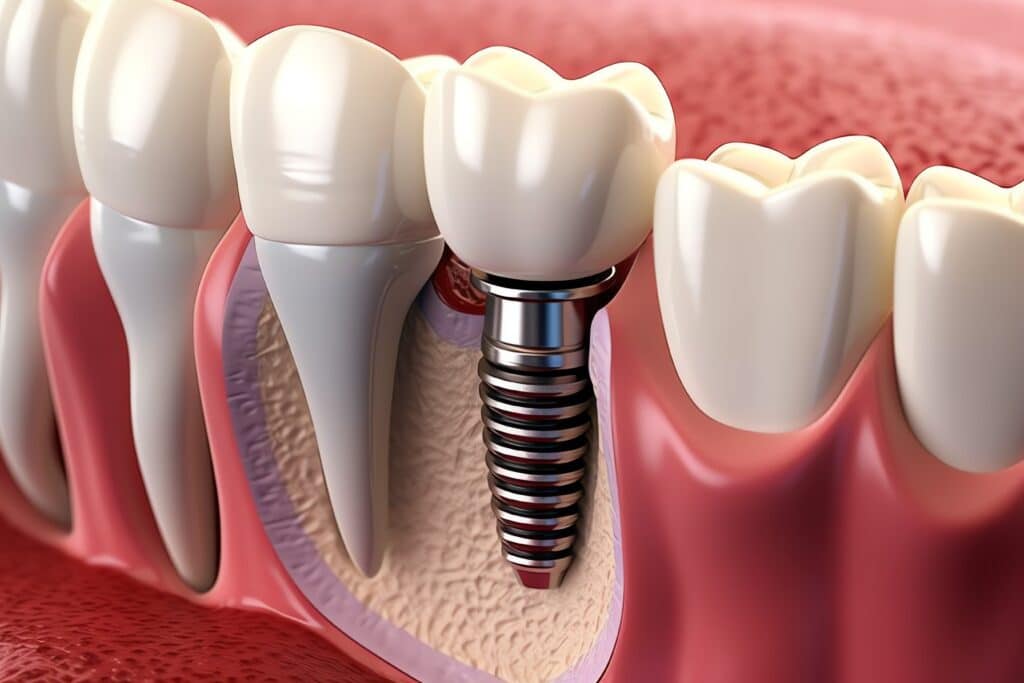

Dental implants are a long-lasting and effective solution for replacing missing teeth, providing a solid and stable base for artificial teeth. This treatment involves several carefully planned stages to ensure the best possible outcome.

First, a titanium post is inserted into the jawbone through a surgical procedure. This post acts as an artificial root, fusing with the bone through a process called osseointegration. Osseointegration is crucial because it ensures that the implant is stable and can effectively withstand chewing forces.

Once the post has fully integrated with the bone, which can take several months, a connector or abutment is placed on top of the implant. This abutment serves as the foundation for the dental crown, which is the visible part of the implant. The crown is custom-made to match the color, shape, and size of your natural teeth, providing a natural and aesthetically pleasing appearance.